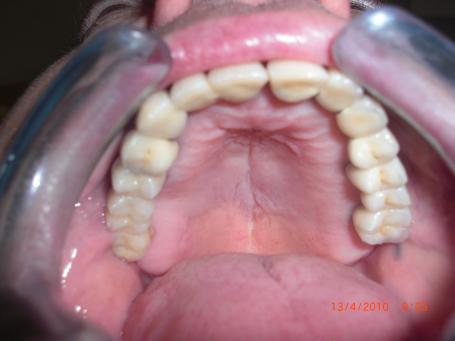

7°)Photo final birdge dentaire céramique

8°) Photo final